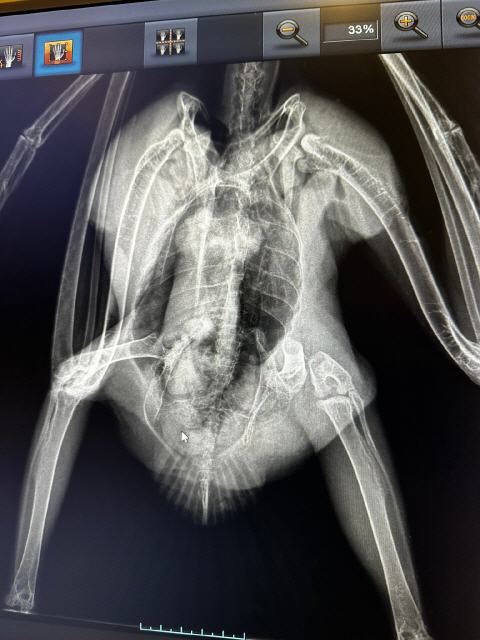

Am Pfingstwochenende 2024 wurden drei junge Wanderfalken in die Auffangstation gebracht. Ein junges Weibchen aus Burgfarrnbach, ein junger Terzel aus Nürnberg und ein weiterer junger Terzel aus Weißenburg. Alle drei waren bei ihren ersten Ausflügen abgestürzt und hatten sich so stark verletzt, dass sie nicht mehr fliegen konnten. Zwei von ihnen waren bereits bekannt, da sie als Jungfalken beringt wurden. Nur der Nürnberger war ein unbeschriebenes Blatt. Nach eingehenden Untersuchungen wurden der Burgfarrnbacher und der Nürnberger Falke in einer Voliere und der leider schwerer verletzte Terzel aus Weißenburg weitergehend untersucht. Bedauerlicherweise stellte sich nach der Anfertigung von Röntgenaufnahmen heraus, dass der Falke mehrere Frakturen und weitere Verletzungen aufwies, sodass er leider eingeschläfert werden musste. Die beiden anderen Patienten erholten sich zum Glück sehr gut von ihren Verletzungen. Da der Brutplatz des Nürnbergers nicht bekannt und der des Burgfarrnbacher Weibchens zu gefährlich erschien, entschied ich zusammen mit Detlef Schiesser (Freund und Beringer der Vogelwarte Radolfzell) beide Vögel dem Falkenpaar in Weißenburg, die einen Jungvogel verloren hatten zur Adoption anzubieten. Am Mittwoch den 29.05.2024 fing ich die beiden Jungfalken aus der Voliere und übergab sie nach abschließender Untersuchung an Detlef Schiesser. Noch an diesem Tag sollten Sie an ihrem neuen Zuhause auf der Spitalkirche in Weißenburg ihre Adoptiveltern und Geschwister kennen lernen. Wir hoffen, dass sie ihren zweiten Start in die Freiheit erfolgreich hinter sich bringen!

Geglückte OP bei Stockente

Die Stockente wurde nach einem Zusammenstoß mit einem Auto aufgesammelt und zu einer Vogelfreundin gebracht. Diese ist eine langjährige Kundin von mir und weiß, dass ich ebenfalls ein großer Vogelliebhaber bin. Die Vogelfreundin unterstützt die Praxis seit vielen Jahren bei der Pflege und Auswilderung von Wildvögeln, für sie kam eine Euthanasie nicht infrage. Ich sollte versuchen, den Ruderfuß der Ente zu retten, was glücklicher Weise auch gelang. Wir hoffen nun, dass sich die Stockente rasch erholt.